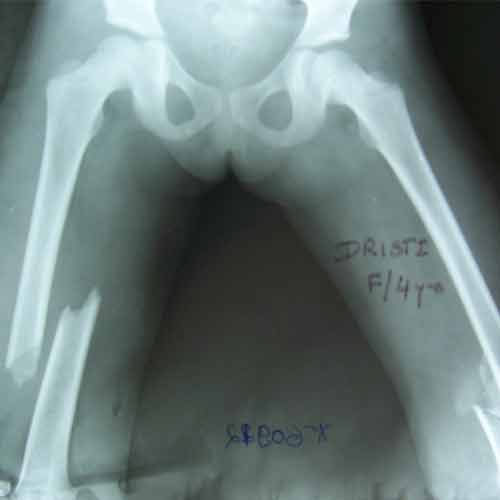

Case:12 Pediatric PolyTrauma

7 Years old female with bilateral fracture shaft femur middle third, lower third junction treated with plating on right side & external fixation & ‘K’ wiring on left side.

Pre-Op

Rt side platting

Lt-side Kwiring+ Ex-fix